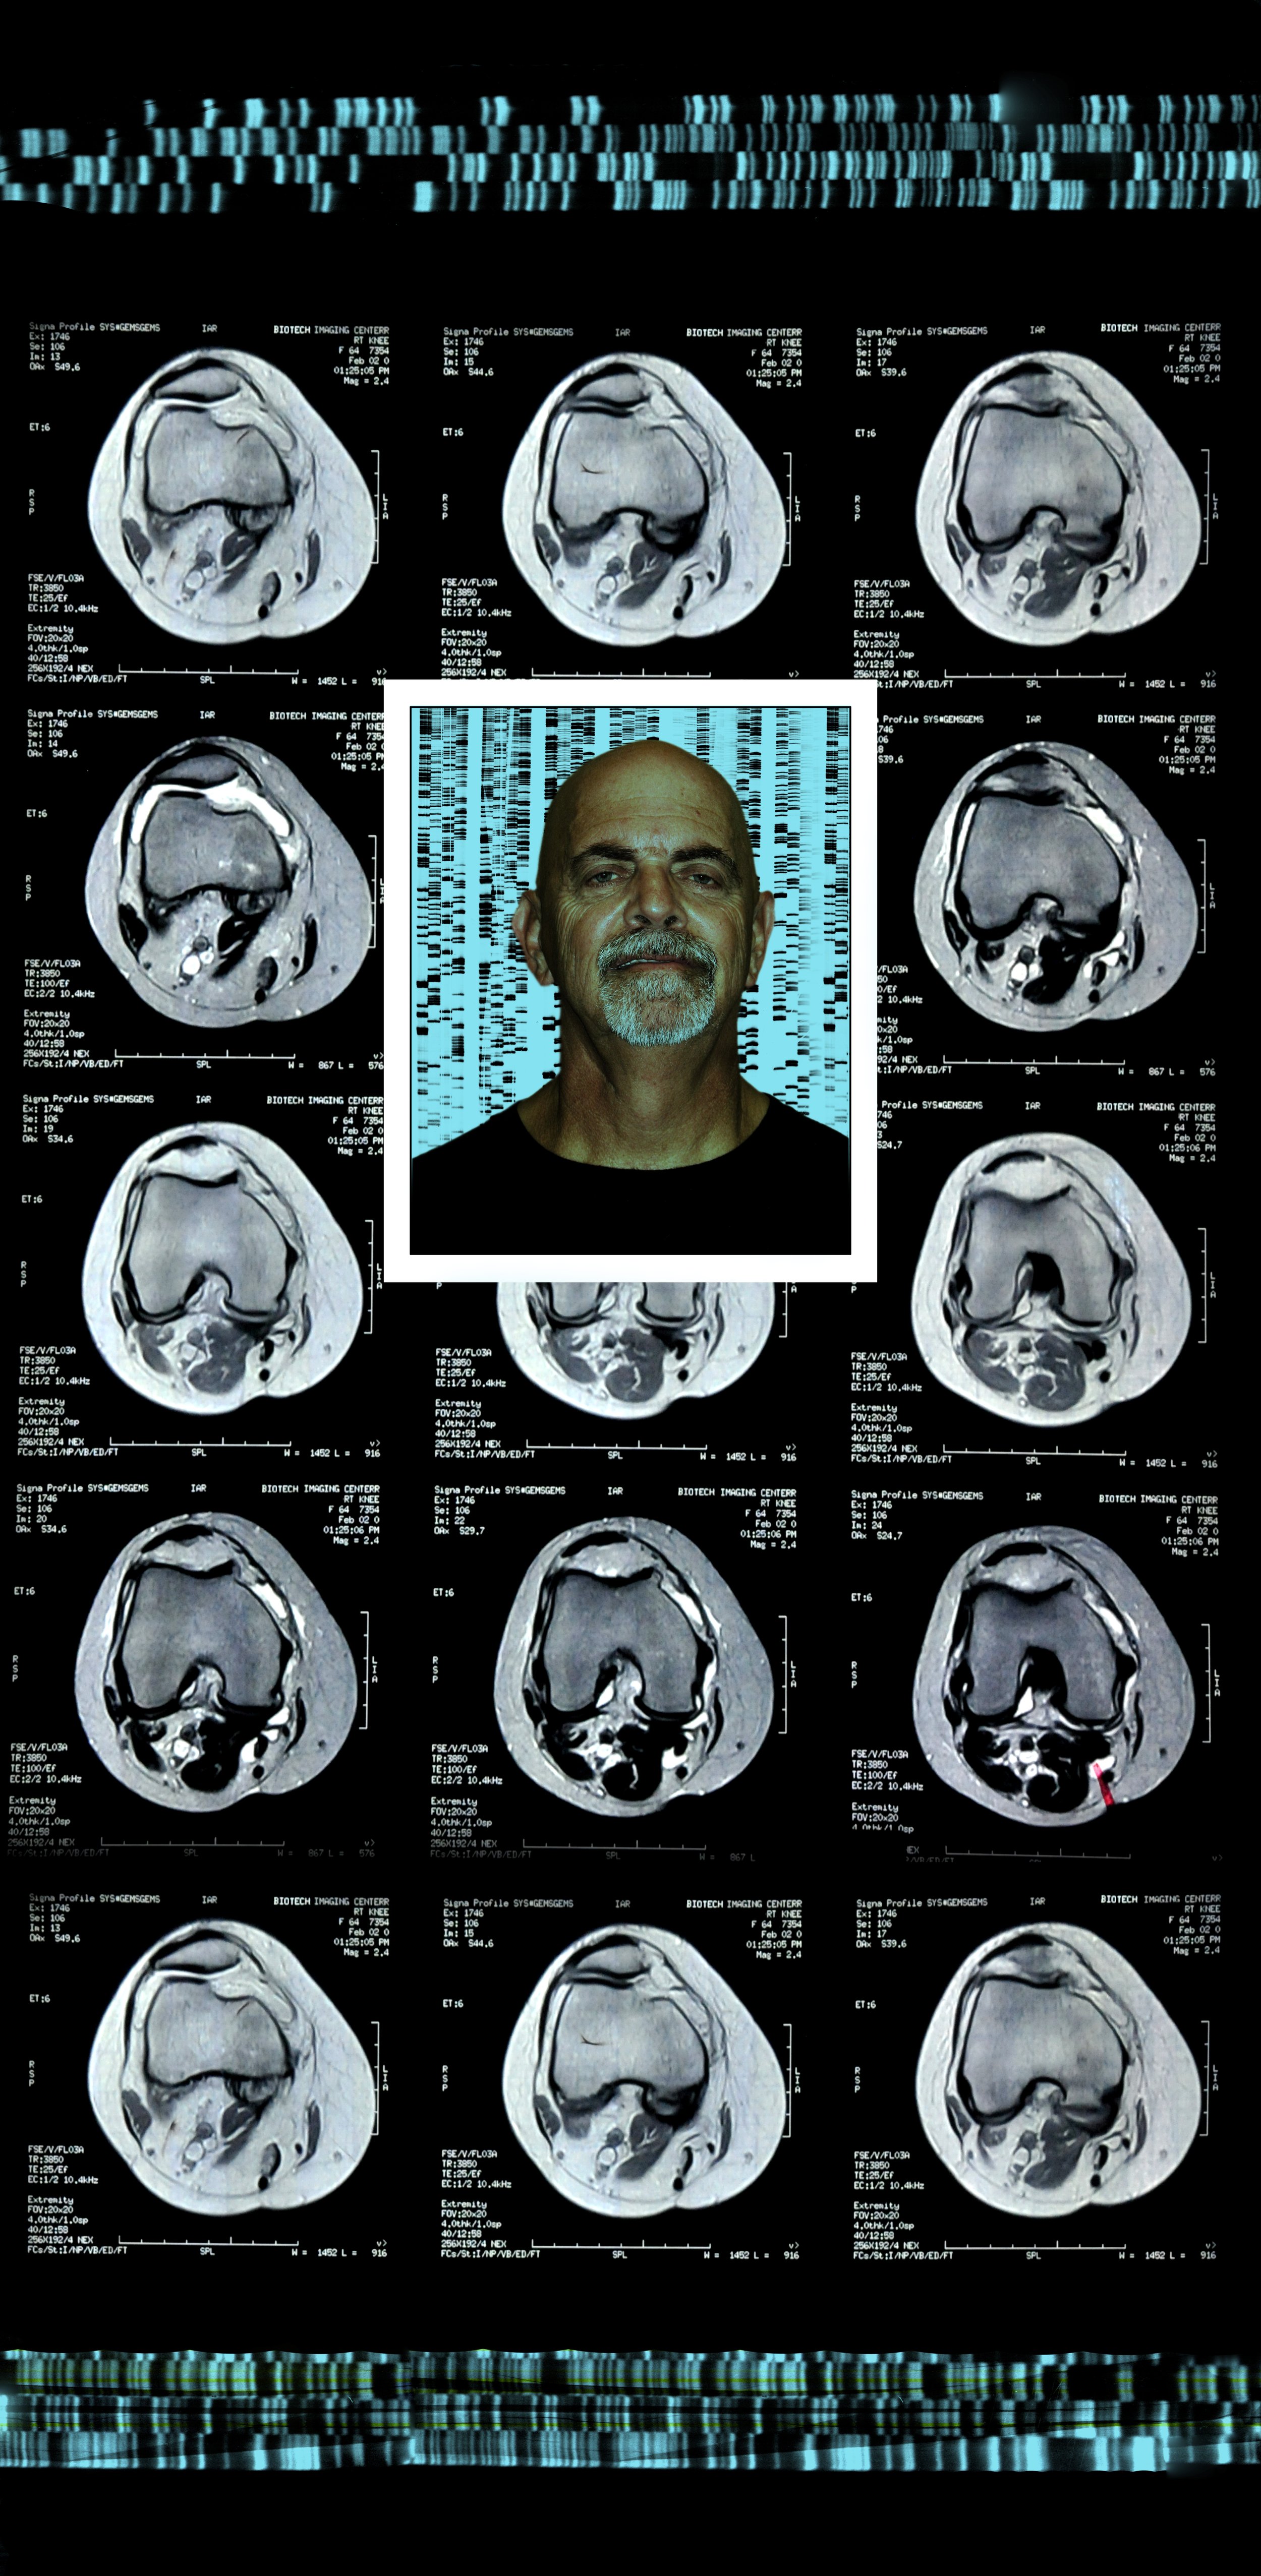

Comprising eight 47” x 23” backlit Plexiglas panels, each work features a portrait, often of individuals from diverse racial, ethnic, and cultural backgrounds. Surrounding these portraits are embedded CT scans, MRIs, and DNA sequencing gels. These medical images, reimagined as expressive symbols, evoke biological inheritance, invisible histories, and interior experience rather than clinical diagnosis.

Used metaphorically, DNA strands suggest ancestral continuity; CT scans and MRIs hint at the unknowable workings of body and psyche; ghostly anatomical forms recall trauma, resilience, and emotional scars. By pairing portraiture with interior imaging, the series questions how we perceive identity. Are we defined by surface appearance—skin, gender, dress—or by memory, genetics, and lived medical experience? Can scientific data be truly neutral, or does it reflect cultural bias and interpretation?

Bald Man 47” x 23”